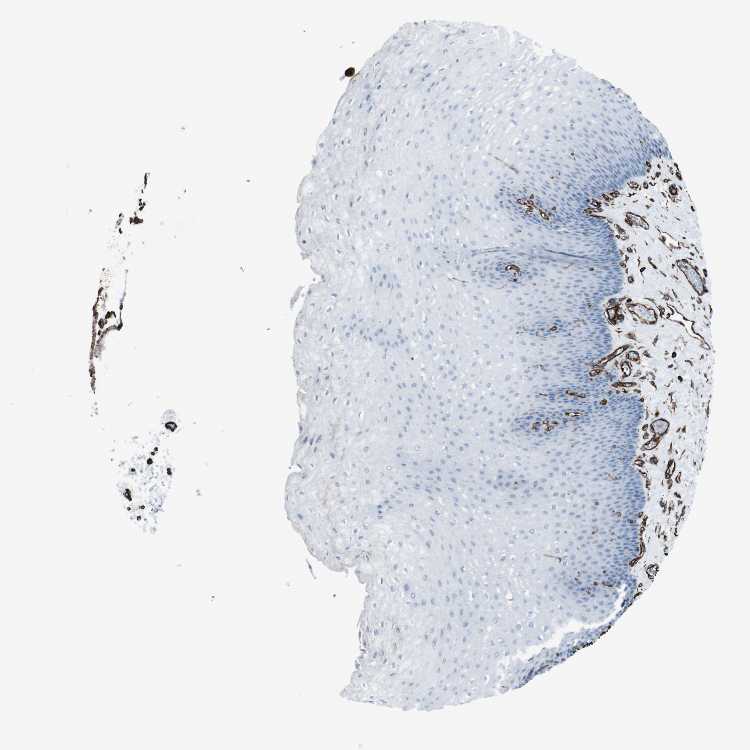

ESOPHAGUS - Antibody stainingi

Antibody staining in the annotated cell types in the current human tissue is reported as not detected, low, medium, or high, based on conventional immunohistochemistry profiling in selected tissues. This score is based on the combination of the staining intensity and fraction of stained cells.

Each image is clickable and will lead to virtual microscopy that enables deeper exploration of all samples and also displays staining intensity scores, fraction scores and subcellular localization as well as patient and tissue information for each sample.

Antibody HPA014357

Squamous epithelial cells Not detected